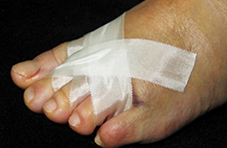

Una vez realizada la osteotomía, las incisiones se suturaron con monofilamento 0000. Se utilizó un vendaje para realizar tracción en los dedos de los pies en dirección medial con una cincha metatarsiana. El paciente salía de quirófano andando con un zapato quirúrgico de suela rígida y plana. Las suturas se retiraron a los siete días y se le mostró cómo cambiar el vendaje para el lavado diario. Se insistió que no debían caminar descalza, sin calzado ni vendaje, para evitar el desplazamiento de las osteotomías (Figura 2).

Figura 2d

Figura 2e

Figura 2. Técnica quirúrgica a) osteotomía DMMO percutánea, b) imagen fluoroscópica de las osteotomías, c) sutura, d) vendaje postquirúrgico con cinchas invertidas para mantener la alineación de los metatarsianos, d, e) vendaje definitivo postquirúrgico, f) paciente al salir de quirófano con apoyo completo y zapato de suela plana y recta